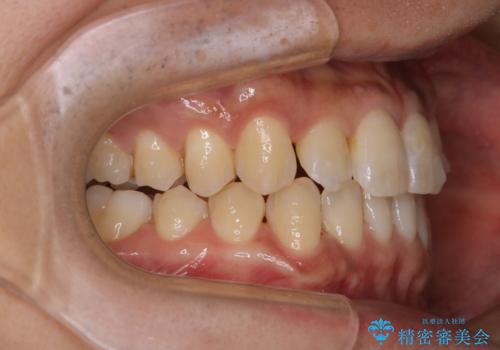

マウスピース矯正インビザライン治療では、歯の表面にアタッチメントという突起を設定します。(アタッチメントは歯の動きを効率的に移動するためのものです)

アタッチメントが歯に付くと、表面が凸凹し磨き残しが多くなったりと、プラークや歯石・着色がつきやすくなることがあります。

矯正治療中もPMTCを定期的に行い、専門的な機械でしっかりと汚れを除去することがおススメです。